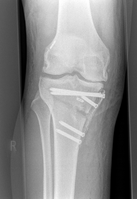

O-Bein präoperativ

Um die Ausrichtung des Kniegelenks zu verändern, sägt der Operateur teilweise in den Ober- bzw. Unterschenkelknochen hinein und „klappt“ diesen auf, sodass ein Spalt im Knochen entsteht. Mit Hilfe des dadurch erzeugten Winkels kann der Arzt die Fehlstellung ausgleichen. Stabilisiert wird die Korrektur – ähnlich wie nach einem Knochenbruch – durch eine Platte und mehrere Schrauben, die nach sechs bis zwölf Monaten wieder entfernt werden können.

Röntgenbild eines Beines im Kniebereich

Korrigierte O-Beinstellung durch Neuausrichtung des Schienbeins (tibiale Kniegelenknahe Osteotomie)